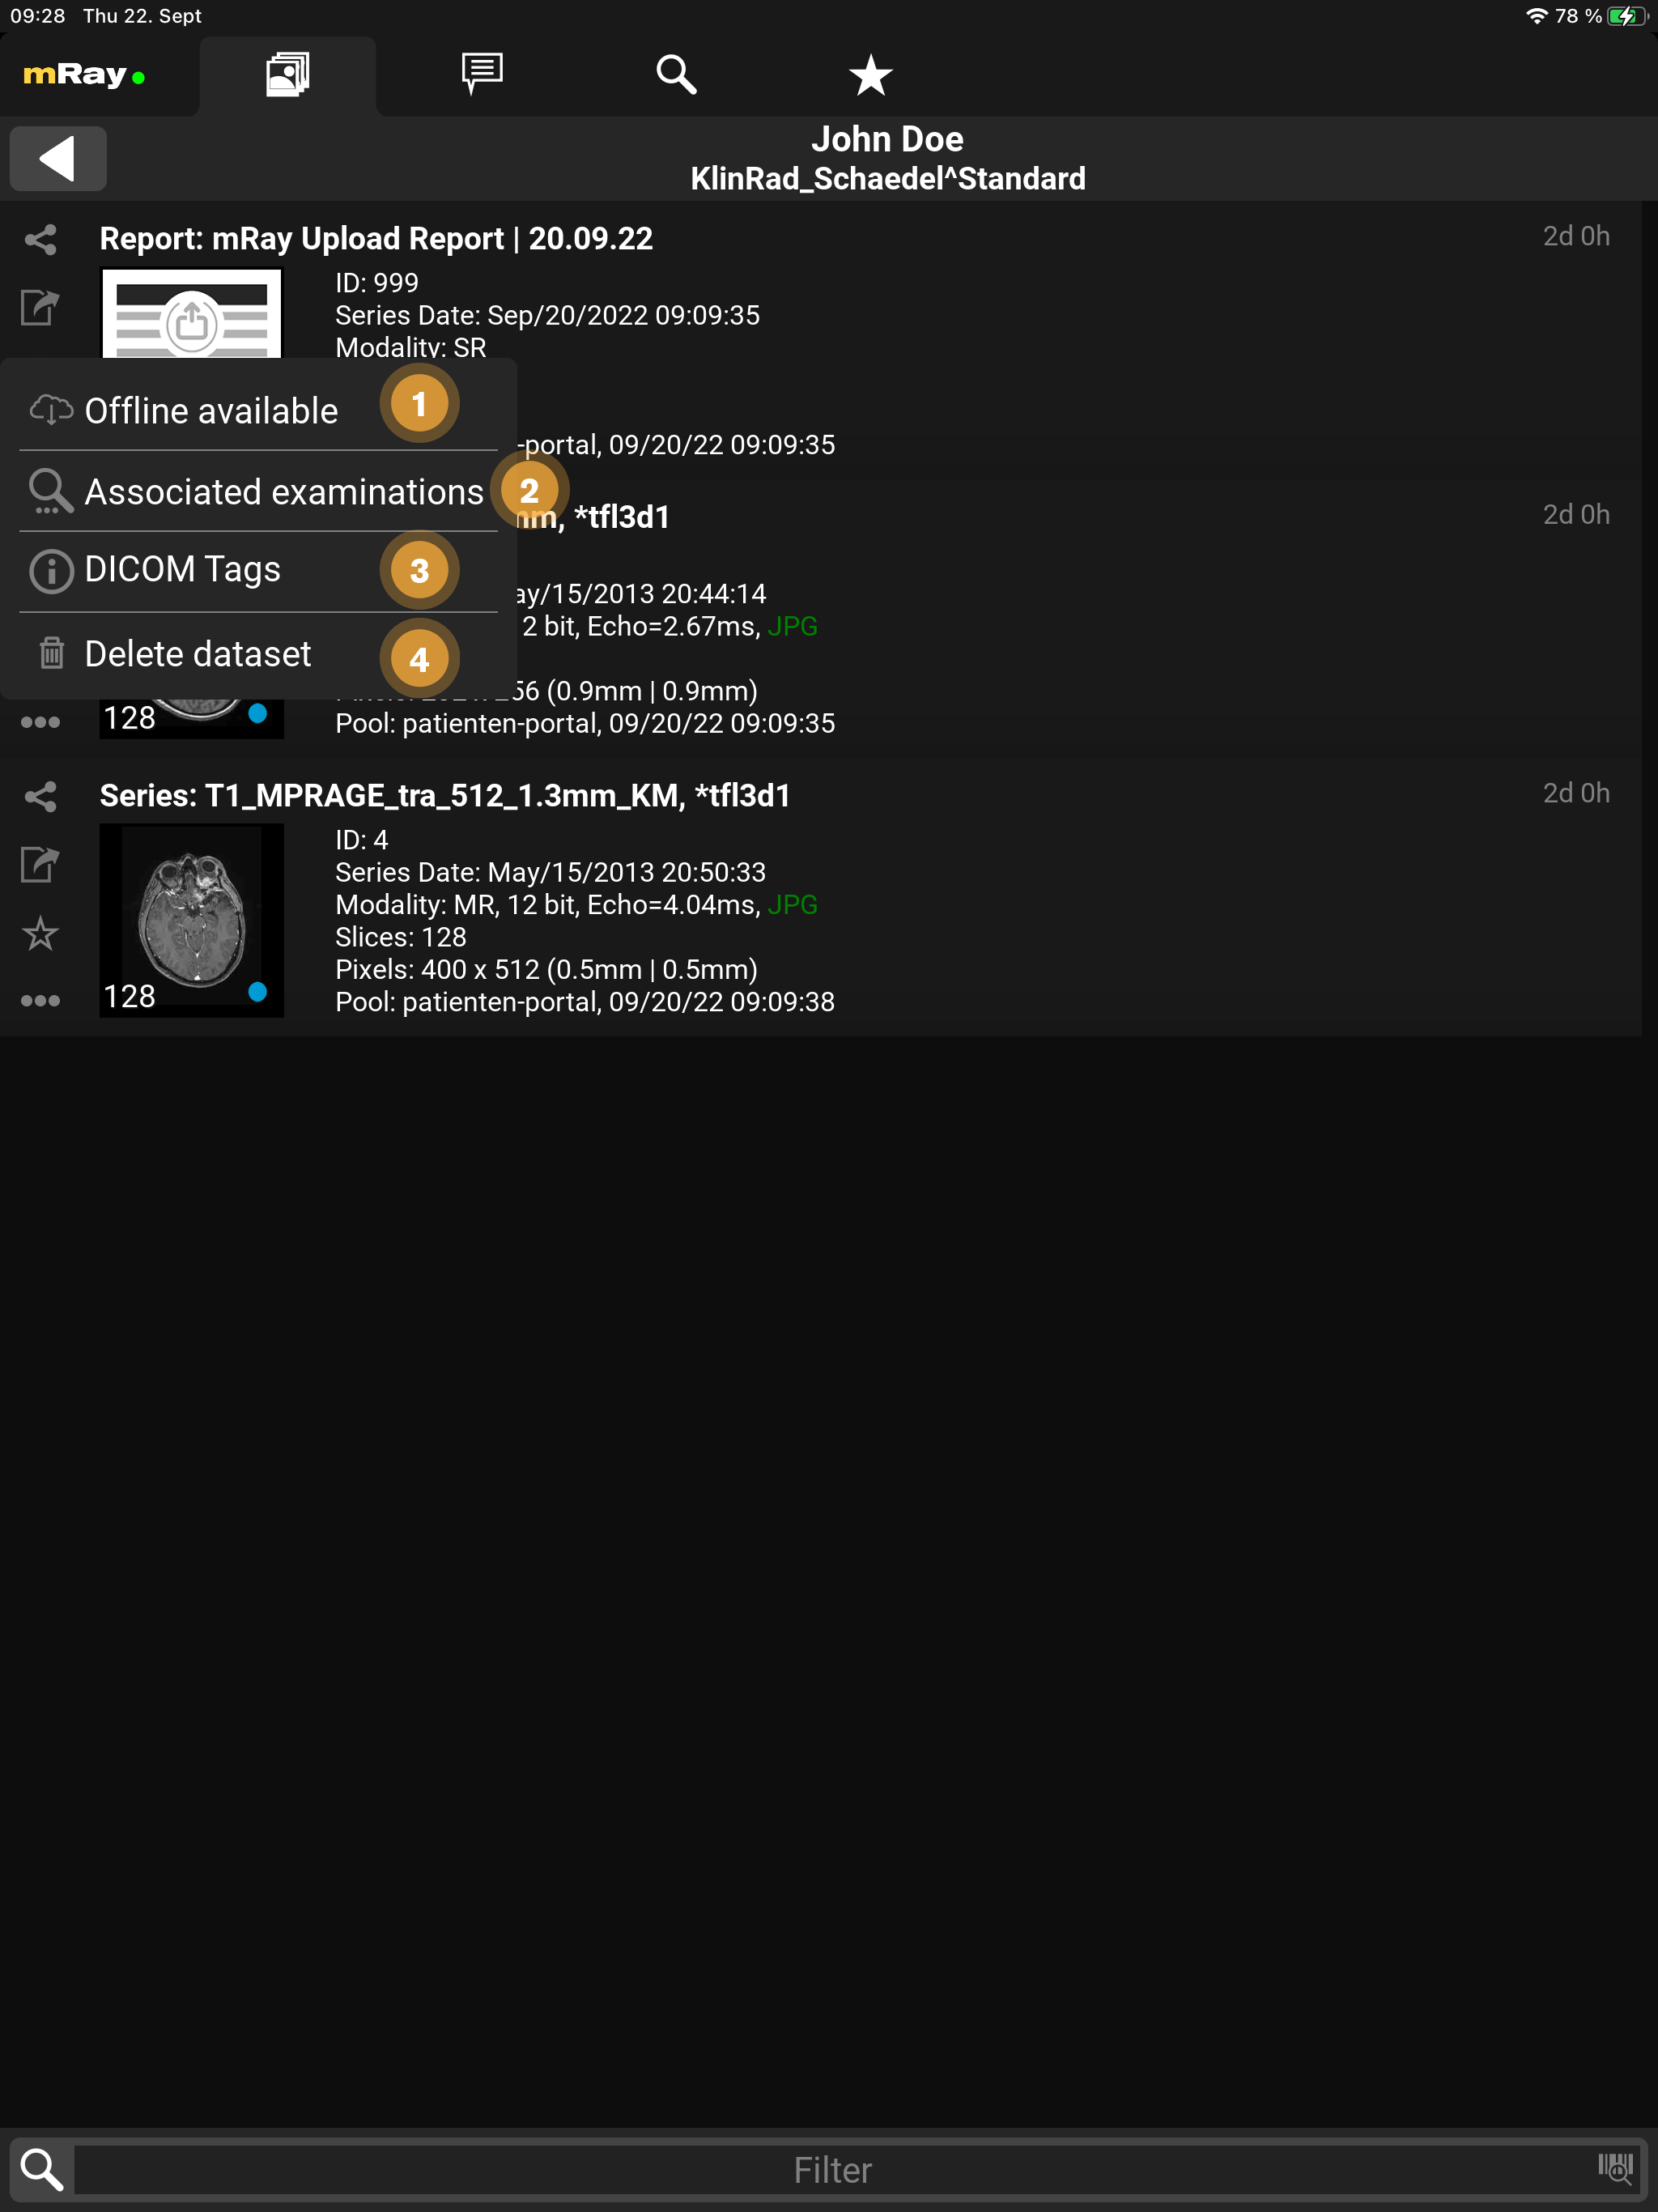

9.2.1. Kontextmenü

Sowohl in der Inbox, als auch in der Serienauswahl lassen sich über das Kontextmenü verschiedene Operationen durchführen.

-

Offline verfügbar: Laden Sie Bilddaten in mRay vor, damit Sie diese auch offline verfügbar haben.

-

Zugehörige Sudien: Finden weitere Studien des Patienten.

-

DICOM-Tags: Falls für den aktuellen Nutzer freigeschaltet, lassen sich über diese Funktion alle DICOM-Tags einblenden.

-

Datensatz löschen: Falls der aktuelle Nutzer die Daten selbst hochgeladen hat, kann er sie hier wieder löschen (auch vom Server).